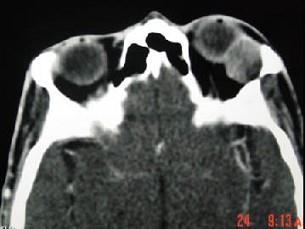

问题 女,36岁,左眼眶外上部可触及一无痛性包块有两年,眼球向内下方突出,CT检查如图,最可能诊断为 ( )

选项 A、淋巴瘤 B、淋巴瘤样增生 C、泪腺恶性上皮性肿瘤 D、炎性假瘤 E、泪腺良性混合瘤

答案 E